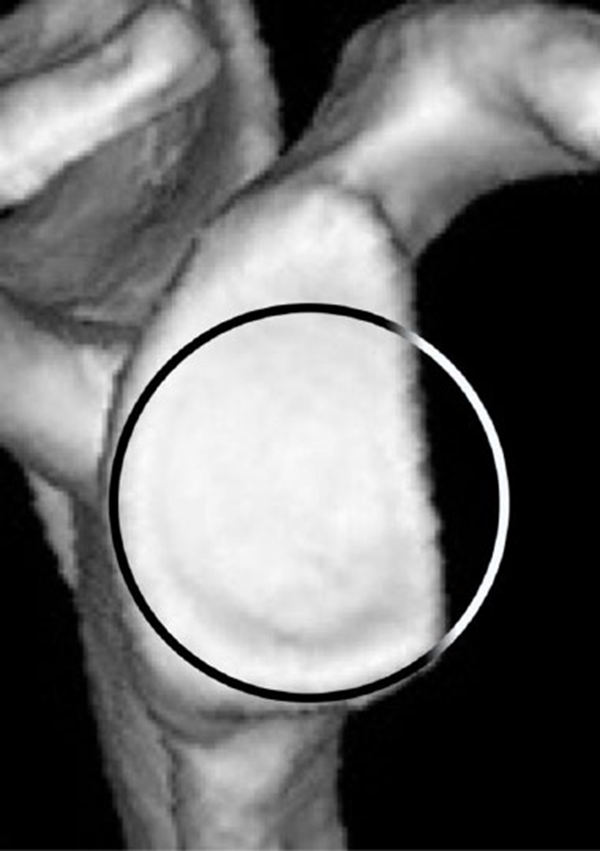

①“最佳拟合圆”法。应用了一个最适合的圆圈,它完美地适合于关节盂的后部和下部。这个圆圈被认为接近关节盂的原始形状。